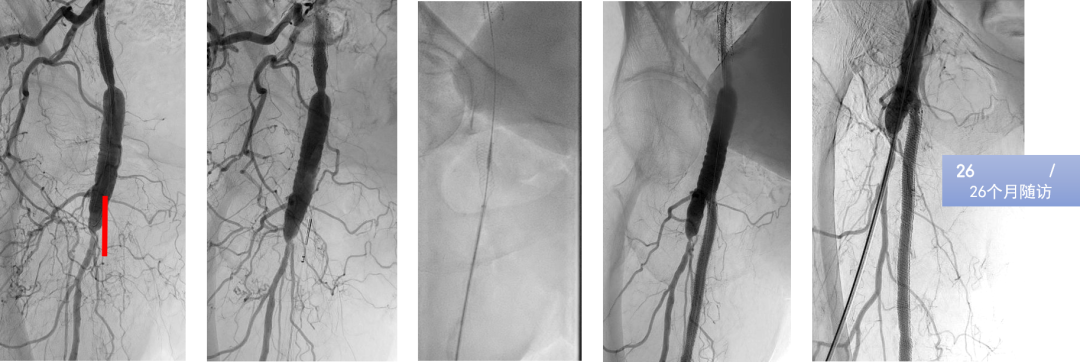

病例示例与技术支持

研究展示了逆行再通中几种高级技术的应用:

Presto技术:通过逆行插入的指引导管辅助,完成治疗。

靶向球囊辅助再入技术(如Outback设备):在顺行球囊标记的引导下,从逆行方向进行精准的真腔再入,高效解决内膜下开通后的对接难题。

这些技术是达成高成功率的重要保障。

CASE 1: